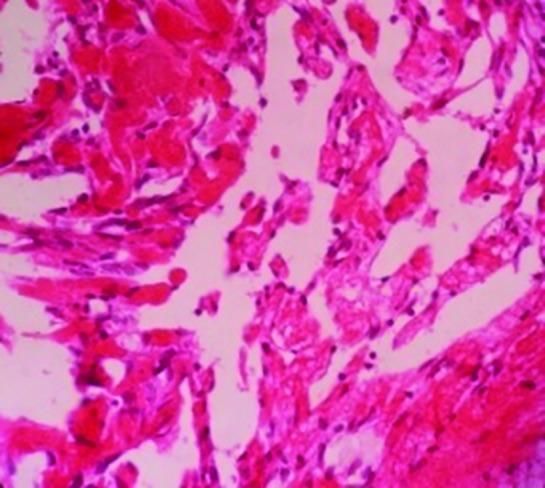

Intravascular papillary endothelial hyperplasia (IPEH) is an uncommon benign vascular disease characterized by endothelial cell proliferation and papillary formation within the lumen of blood vessels arising from an organizing thrombus. The occurrence of this uncommon lesion is about 2% of all vascular tumors. IPEH mostly occurs in the 5th decade of life, and there is no gender or age predilection. Nevertheless, some studies have suggested that IPEH is more common in women than in men. The clinical features are mostly asymptomatic, and the lesion is typically characterized as a small, firm, slightly elevated mass with red to blue discoloration of the overlying skin. The main diagnosis of the lesion is based on histological examination. The most common locations of IPEH are head and neck, fingers, and trunk. The occurrence of IPEH in the urethra is extremely rare, with only a few cases having been reported in the literature. We describe a 70-year-old woman with a complaint of dysuria and urethral bleeding of 3 days' duration. Clinically, the lesion was a palpable firm mass in the urethra. Urethrocystoscopy illustrated a dark mass, a few millimeters in size, with bleeding. Histologic findings revealed dilated blood vessels with multiple papillary projections into the lumen. Thus, based on these findings, a final diagnosis of Masson's tumor was confirmed. According to clinical and radiographic findings, this lesion is similar to malignant lesions and its accurate diagnosis is based on microscopic findings. Therefore, awareness of the microscopic characteristics of this tumor is very important for clinicians to rule out the presence of malignant vascular lesions and to avoid unnecessarily aggressive therapy.

血管内乳头状内皮增生(IPEH)是一种罕见的良性血管疾病,其特征是由机化血栓形成的血管腔内内皮细胞增生和乳头形成。这种罕见病变的发生率约占所有血管肿瘤的2%。IPEH大多发生在50岁左右,无性别或年龄倾向。然而,一些研究表明,IPEH在女性中比在男性中更常见。临床特征大多无症状,病变通常表现为一个小的、坚实的、轻度隆起的肿块,其上覆皮肤有红至蓝色变色。病变的主要诊断基于组织学检查。IPEH最常见的部位是头颈部、手指和躯干。IPEH发生于尿道极为罕见,文献中仅报道过少数病例。我们描述了一名70岁女性,主诉持续3天的排尿困难和尿道出血。临床上,病变是尿道内一个可触及的坚实肿块。尿道膀胱镜检查显示一个几毫米大小的深色肿块,伴有出血。组织学检查结果显示血管扩张,有多个乳头状突起伸入管腔。因此,基于这些发现,确诊为马松瘤。根据临床和影像学检查结果,该病变类似于恶性病变,其准确诊断基于显微镜检查结果。因此,了解这种肿瘤的微观特征对于临床医生排除恶性血管病变的存在以及避免不必要的积极治疗非常重要。